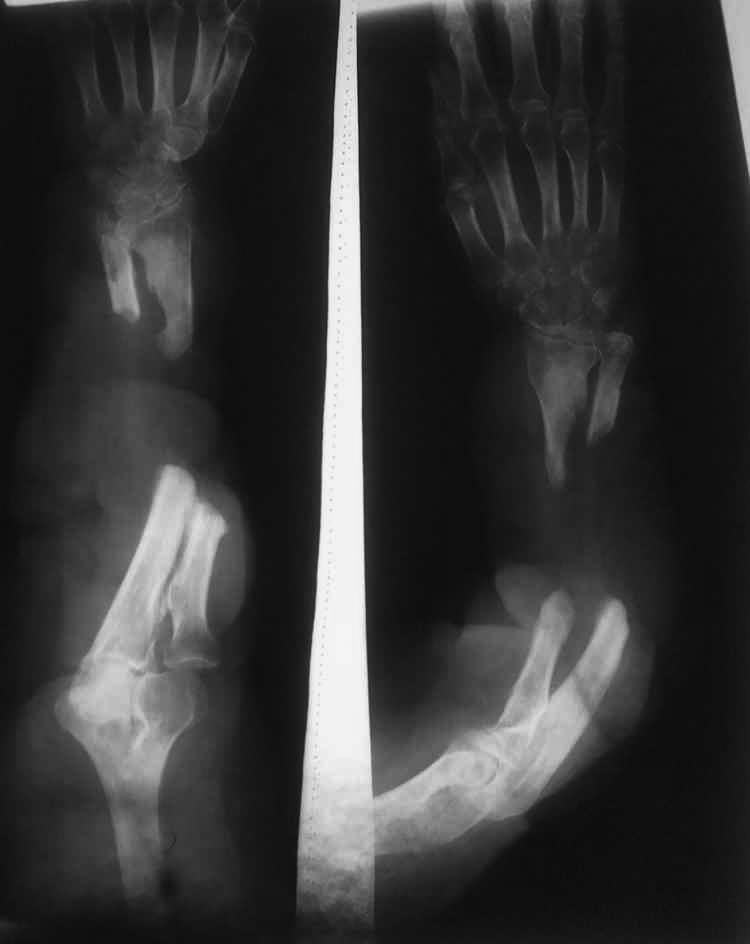

Я имел аналогичного пациента 24 года назад, когда я начинал работать в Америке.

Поступила больная с Мексики с остеомиелитом обеих костей и большим дефектом обеих костей.

Мы применили методику Илизарова. Замещали дефект костей с помощью направляющих спиц.

Одна спица была проведена через Лучевую кость и инромедулярно доходила до проксимальной части лучевой кости, где мы сделали остеотомию и с помощью крючка зацепили этот фрагмент.

С локтевой костью мы поступили аналогично, провели интромедулярно с проксимальной частi локтевой кости до дистальной. В дистальной части локтевой кости сделали остеотомию и с помощью крючка на спице зацепили этот фрагмент. Кости предплечья зафиксировал в Аппарате Илизарова и спицы для тяги закрепили на кольцах.

Результат получился отличный, даже удалось сохранить ротационные движения в предплечье. К сожалению не могу Вам выслать рентгенограммы. т.к. я сейчас работаю в другом ( Hospital for Special Surgery) госпитале.

Согласен с Леонидом Николаевичем Соломиным. Возможно, после резекции концов и замера дефекта получится обойтись не "трансплантатами", а одним трансплантатом, в виде 2-хстволки. Тем более, речь о восстановлении длины предплечья не идет.

Прежние неумелые действия привели к несостоятельности мягких тканей, и следующая процедура может осложниться более печальными последствиями. Поэтому восстановление надо провести с учетом тех ошибок и максимально щадящим методом…

Среди классических методов замещения дефектов костей предплечья доминирует метод Илизарова и также алло- или аутокостная пластика. Небольшие дефекты закрываются трех-кортикальным трансплантатом из крыла, а большие дефекты лучше малоберцовой на сосудистой ножке или без.

Много единичных публикаций по успешному применению кейджей при дефектах костей, и серию из 6 публиковал Naftaly Attias, MD в 2006 году. Management of Large Segmental Long Bone Defects Using Cylindrical Titanium Mesh Cages, где доказал, что успешность операции зависит от мягкотканого покрова! Основным условием применения кейджа является не-контаминированные поверхности, т.е. чистые дефекты. После резекции опухолей или после врожденных ложных суставов (более благоприятная среда) даже самые огромные дефекты перестраивается лучше, чем в инфицированной среде.

На первом этапе, для улучшении кондиции мягких тканей, можно применить аппарат, но с обязательным изучением состояния сосудов. А профилактику повреждения сосудов во время введения спиц надо делать под ультразвуком, иначе..! В зависимости от опыта можно продолжать лечение аппаратом Илизарова, но мне кажется, что прикрепить лучевую к локтевой (оne bone arm) - легче восстановить, чем обе кости. Здесь схематический рисунок.

На сосудистой ножке малоберцовая и минимальная фиксация. Ради защиты хрупкого кровообращения внутрикостная или экстрамедуллярная фиксация категорически запрещается. Для соединения сосудов проксимально иногда надо делать крюк Vein graft от нижних отделов плеча. Ступенчатая остеотомия в дистальном отделе минимизирует фиксацию, а проксимально внутри канала и снаружи шурупами. Дистально Sauve Kapandji и дополнительный легкий наружный фиксатор создаст достаточную стабильность!